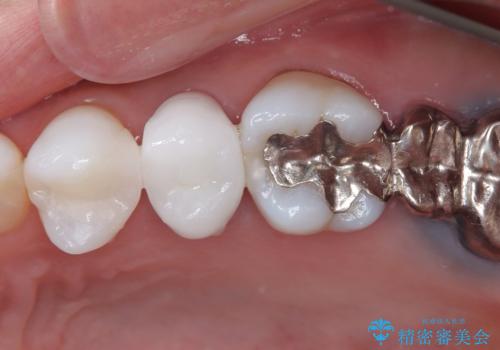

- 20年ほど前に被せた前歯のメタルボンドクラウンの色合いを気にして来院された患者様です。

2歯をオールセラミッククラウン(ジルコニアクラウン)にて補綴することとしました。

裏打ちが金属の場合、どうしても金属色を遮蔽しないとならないため、透明感のない色合いとなってしまいます。

土台の金属はグラスファイバーを含有したものに、クラウンの土台は強化セラミックとすることで、自然な前歯に仕上がりました。